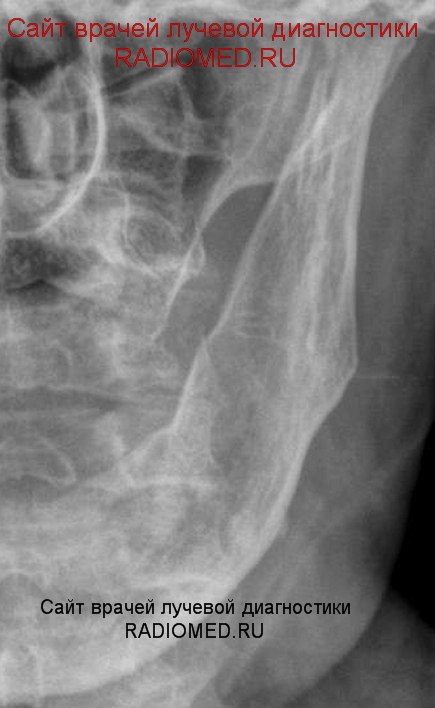

Катенёв Валенти... Дата публикации 28.08.2009, 00:16 Варианты ответов. 1. Остеомиелит. 2. Ячеистая форма гигантоклеточной опухоли. 3.Гигантоклеточная репаратичная гранулёма. 4.Гемангиома. 5. Фиброзная дисплазия. 6. Туберкулёз. 7. Остеосаркома. 8. Адамантиома. (Изображения от "Татьяны Валентиновны") Пт, 28/08/2009 - 13:39 #1 tatyana Не на сайте Был на сайте: 4 года 1 месяц назад Зарегистрирован: 24.06.2009 - 08:33 Публикации: 2090 ??????????? Валентин Львович! "самоуверенность дилетантов - предмет зависти профессионалов" Пт, 28/08/2009 - 14:00 #2 Ola-la Не на сайте Был на сайте: 10 месяцев 2 недели назад Зарегистрирован: 06.12.2008 - 09:33 Публикации: 1786 Предположу № 2. https://www.instagram.com/pediatricradiology/ Пт, 28/08/2009 - 14:56 #3 OPEXOB Не на сайте Был на сайте: 9 лет 11 месяцев назад Зарегистрирован: 26.07.2008 - 10:02 Публикации: 280 Ячеистая форма гигантоклеточной опухоли. Пт, 28/08/2009 - 18:49 #4 Ермолаев Не на сайте Был на сайте: 8 лет 10 месяцев назад Зарегистрирован: 07.02.2009 - 16:33 Публикации: 670 Уважаемые коллеги! Можно выбрать два варианта 2 и 3? dok Пт, 28/08/2009 - 19:13 #5 Almo Не на сайте Был на сайте: 11 часов 28 минут назад Зарегистрирован: 28.09.2008 - 18:50 Публикации: 8262 №2 ? Пт, 28/08/2009 - 21:43 #6 v1tal Не на сайте Был на сайте: 4 года 9 месяцев назад Зарегистрирован: 07.06.2008 - 19:41 Публикации: 1779 Я тоже за 2й вариант. "Знаешь, у некоторых врачей есть комплекс мессии — им необходимо спасать мир. А у тебя комплекс Рубика — тебе необходимо решать головоломки." Пт, 28/08/2009 - 22:35 #7 tatyana Не на сайте Был на сайте: 4 года 1 месяц назад Зарегистрирован: 24.06.2009 - 08:33 Публикации: 2090 а я считаю в дифференциально-диагностическом ряду не хватает адамантиномы! "самоуверенность дилетантов - предмет зависти профессионалов" Пт, 28/08/2009 - 23:20 #8 Катенёв Валенти... Не на сайте Был на сайте: 7 лет 3 недели назад Зарегистрирован: 22.03.2008 - 22:15 Публикации: 54876 Добавлено.

Ячеистая форма гигантоклеточной опухоли.

а я считаю в дифференциально-диагностическом ряду не хватает адамантиномы!